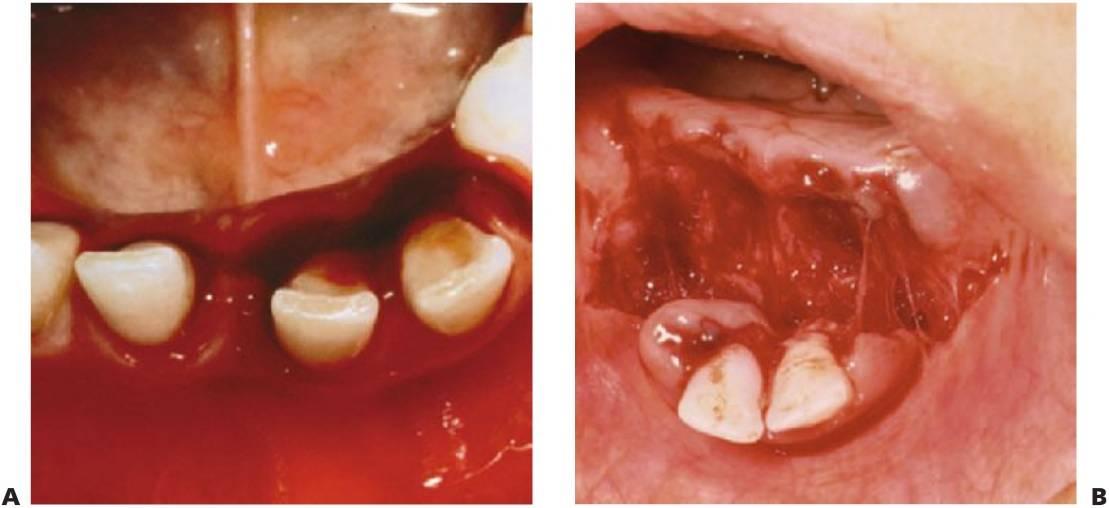

El tratamiento de los traumatismos dentoalveolares, que suele resultar angustioso para los niños y para los padres (fig. 7.1), con frecuencia resulta también difícil para el especialista, si bien se encuentra entre las causas más habituales de visita del niño al odontopediatra. La urgencia del paciente debe constituir una rutina para el especialista y siempre debe elaborar se un exhaustivo examen del niño antes de comunicar a los padres las eventuales necesidades de tratamiento, pues muchos casos podrían carecer de la gravedad que parecía en un principio. Ante todo, se debe tranquilizar tanto a los padres como al niño, pues un traumatismo no sólo compromete una dentición sana, sino que puede también ocasionar un defecto que afecte a la autoestima y a la calidad de vida del paciente y le obligue a un mantenimiento odontológico de por vida.

La región orofacial sufre la mayor afectación de traumatismos durante los episodios de maltrato infantil (fig. 7.2) y estos traumatismos no accidentales tienen como resultado diferentes tipos de lesiones, como las lesiones que no concuerdan con el relato ofrecido, los hematomas en tejido blando que no cubren prominencias óseas, las lesiones que adquieren la forma de un objeto reconocible o la multitud de lesiones que aparecen en el mismo niño a diferentes edades; asimismo, las marcas de mordeduras en niños se consideran maltrato infantil hasta que se prue be lo contrario. Para establecer la adecuada notificación, tratamiento y prevención de más lesiones, deben ser del total conocimiento del especialista tanto las características y las conclusiones del diagnóstico de maltrato infantil como el protocolo para denunciar tales hechos.